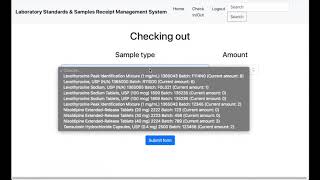

Drug Inventory Program for Primary Healthcare Clinics by Ali Ganjizadeh

Medical Drug Inventory: suitable for pharmacists and anyone in charge of drugs supply.